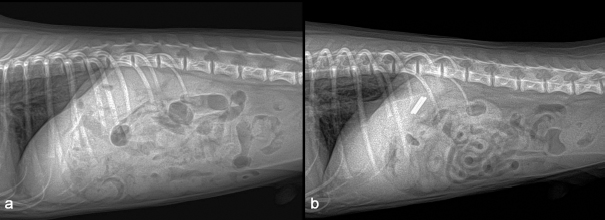

A 1-year-old neutered male Maltese dog weighing 1.4 kg was referred to the Veterinary Teaching Hospital showing microhepatica (Fig. 1a) and hyperammonemia. The dog did not show clinical signs related to portosystemic shunt previously. Although its postprandial ammonia level was in the reference range [18 μmol/l, reference interval (RI): 0–98 μmol/l], hypoalbuminemia (2.1 g/dl, RI: 2.6–3.3 g/dl) and increased levels of serum bile acid (177 μmol/l, RI: 0–25 μmol/l), alanine transaminase (ALT) (254 IU/l, RI: 21–102 IU/l), and alkaline phosphatase (ALP) (1347 IU/l, RI: 29–97 IU/l) were identified. No abnormalities, including cardiac murmur, were observed during physical examination. For a more thorough examination, computed tomography was used, and a CPSS (porto-caval shunt) was diagnosed (Fig. 2a and b). After preoperative medical stabilization, surgery was performed for shunt attenuation. Anesthesia was induced with propofol (8 mg/kg, IV) and maintained by isoflurane. Perioperative pain was managed by tramadol (5 mg/kg, IV). From the xiphoid process to the pubis, a standard ventral midline approach was taken. After dissecting the shunt from surrounding tissues, portal pressure was measured from the jejunal vein. Baseline portal pressure was measured to be approximately 7–8 mmHg (RI: 6–10 mmHg). It increased to 13–14 mmHg after temporary complete occlusion of the shunt. The shunt was attenuated using a cellophane band. The abdominal cavity was closed in a routine manner. Its recovery from anesthesia was uneventful. Postprandial serum bile acid (12 μmol/l), albumin (2.6 g/dl), and ALT (29 IU/l) levels returned to their normal ranges at 1 month after the operation. Its serum ALP level also decreased to 430 IU/l, although it was above the RI. An increase in liver size was observed by abdominal radiographs 1 month after surgery (Fig. 1b). Because the majority of the CPSS anomalies were cured throughout the follow-up period, the dog was able to return to normal life without the need for supporting medicine. One year after surgery, the dog was presented to the Veterinary Teaching Hospital for exercise intolerance. Blood gas analysis revealed hypoxemia (73.6%, RI: 95%–99%). A cardiac murmur was auscultated. When compared with thoracic radiographs evaluated at the time of the operation (Fig. 3a and b), the vertebral heart scale increased from 10 to 11.7, indicating generalized cardiomegaly (Fig. 3c and d). Following echocardiography revealed ASD and pulmonary hypertension (Fig. 4a and b). A bubble study confirmed right-to-left shunt. Surgical or interventional therapy was not contemplated due to the dog's tiny size (1.7 kg) and reversed interatrial shunt. Thus, medical treatment was performed to reduce pulmonary hypertension (sildenafil, 1.5 mg/kg, PO, q12 hours). Hypoxemia was improved (94%) after a month of treatment. The dog's activity intolerance had been overcome, according to the owner. As a response to the medical treatment was generally good, therapy was still maintained without changing medication for the next 16 months after diagnosis of the ASD.

Fig. 1. Preoperative abdominal radiograph revealed microhepatica (a). An increased liver size was seen in abdominal radiograph one month after the operation (b).